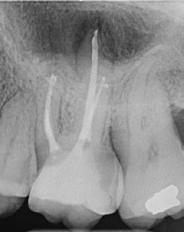

2. Kemomechanikai rendszerek Túlnyomásos rendszerek Alulnyomásos rendszerek

1. ábra: A 12. fog - a röntgenfelvételen nagyméretű periapikális elváltozás látható. A tünetmentes fogat ISO 25/.06 TF Adaptive reszelővel (Kerr Dental) preparáltuk. – 2. ábra: A 12. fog gyökércsatornájának tömését ásványi trioxid aggregátummal (ENDOSEAL MTA, Maruchi) végeztük. Figyeljük meg az apikális elágazás lezárását, ami az apikális terminus hatékony tisztítása és dekontaminálása miatt lehetséges. A gyógyulás 12 hónap elteltével csaknem teljes volt. – 3. ábra: 33. fog - a páciensnél egy bukkális sinus traktus volt látható, amely röntgenfelvételen a 32. és a 33. fog közötti területnek felelt meg. A CBCT és a röntgenfelvétel nagyméretű periradikuláris elváltozást mutatott, különösen a disztális oldalon. A preparálást 20/,07v ProTaper Gold (F1; Dentsply Sirona) készülékkel végeztük. – 4. ábra: A 33. fog gyökércsatorna obturációját sealer és hordozó alapú guttapercha (AH Plus és Thermafil, Dentsply Sirona) segítségével végeztük. A hat hónappal a műtét után végzett röntgenellenőrzés azt mutatta, hogy több oldalsó csatorna feltöltődött, és a gyógyulási folyamat folyamatban van.

keletkeznek [25-29]. A másodlagos kavitációs buborékok összeomlásuk során a csatornafalak közvetlen közelében vannak, nyírófeszültséget és örvényes áramlásokat generálva, amelyek képesek eltávolítani a törmeléket, a kenetréteget és a biofilmet a gyökércsatorna felszínéről, valamint a fel nem fedezett és műszerrel nem rendelkező anatómiai területekről, például az isztmuszokból, az oldalsó csatornákból, a hurkokból és a ramifikációkból, ezáltal tovább fokozva a tisztítási és dekontaminációs mechanizmust (1-4. ábra). A gyökércsatorna mentén létrejövő fokozott nyomás következésképpen az irrigálószereknek a dentinális tubulusokba való behatolásának mélységét is növeli [25-28].